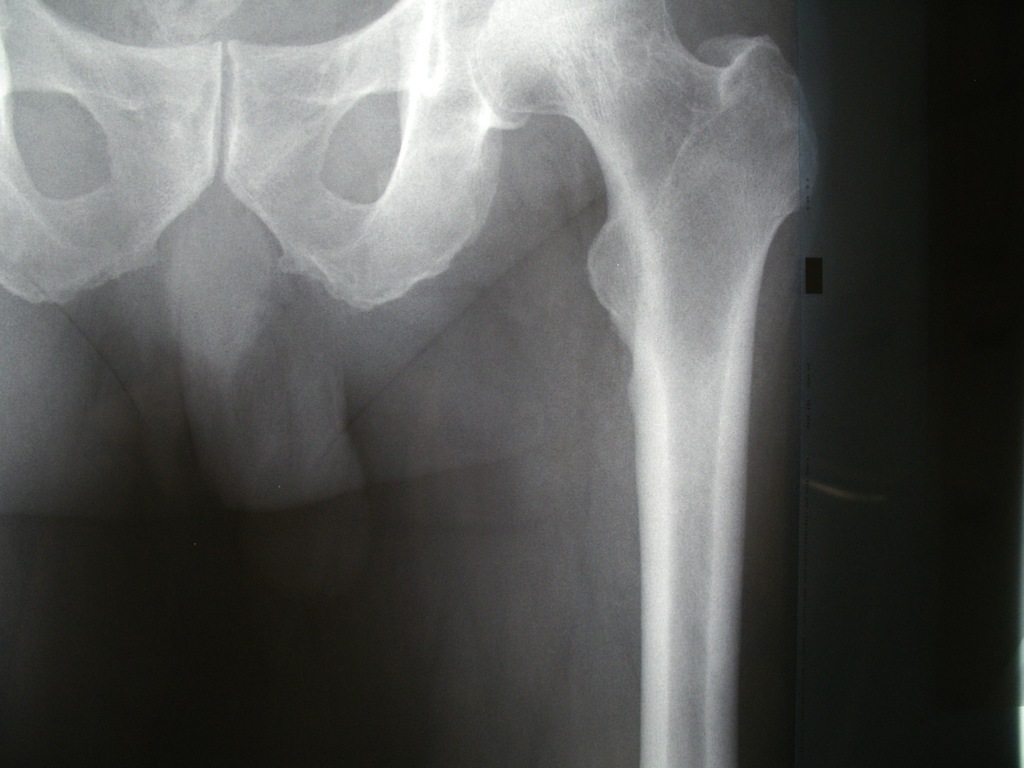

次は足です。こちらが正常な状態ですが、 動脈が極端に硬くなるとこのようにレント...

次は太ももの血管です。正常ですとこのように骨だけが白く写るわけですが、動脈が極端...